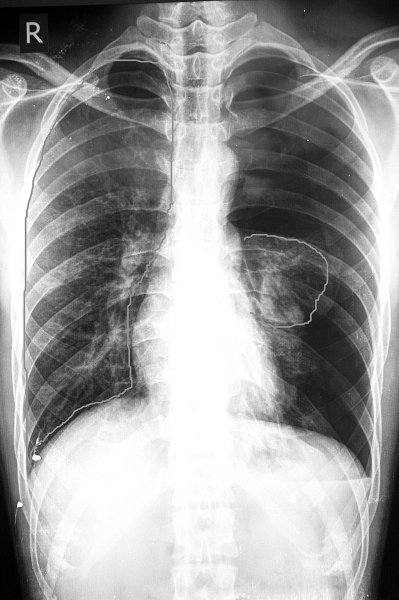

如图左边大圈是正常的右肺,右边小圈是异常的左肺。

经心电图、肝脾彩超、胸片等相关检查,确诊小方患的是自发性气胸。拍出的胸片尤其惊人,左肺压缩达90%,基本难见踪迹。该院胸外科吴中权教授安慰小方:其实左肺的异常与拔火罐并无直接关系。